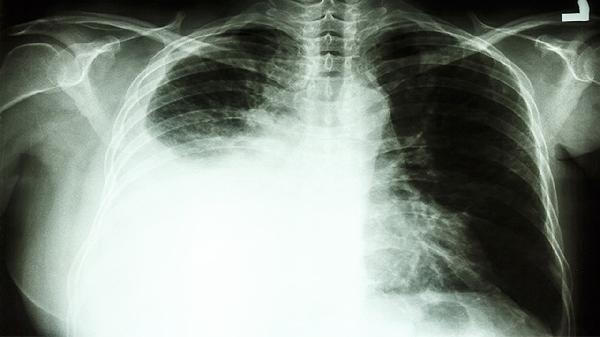

CT检查能清晰显示肺部结节或肿块的部位、大小、密度及边缘特征,对早期肺癌筛查具有较高敏感性。低剂量螺旋CT已被推荐为肺癌高危人群的常规筛查工具,可检出直径小至2毫米的微小结节。通过动态增强CT还能观察病灶的血供特点,磨玻璃结节、分叶征、毛刺征等典型表现可提示恶性可能。但炎症、结核等良性疾病也可能出现类似影像学表现。

部分特殊类型的肺癌在CT上可能呈现不典型特征,如贴壁生长的肺泡细胞癌早期可能仅表现为淡薄磨玻璃影。小于8毫米的肺结节在CT上难以定性,需要长期随访观察变化。部分中央型肺癌可能被纵隔结构遮挡,导致CT检出率下降。某些罕见病理类型如类癌、肉瘤样癌的影像表现缺乏特异性。